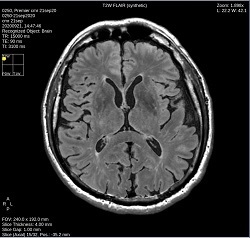

- By default, a 6-viewport display is launched with 6 unique MAGiC images.

Click T2W FLAIR to change the image contrast to synthetic T2 FLAIR-weighted.